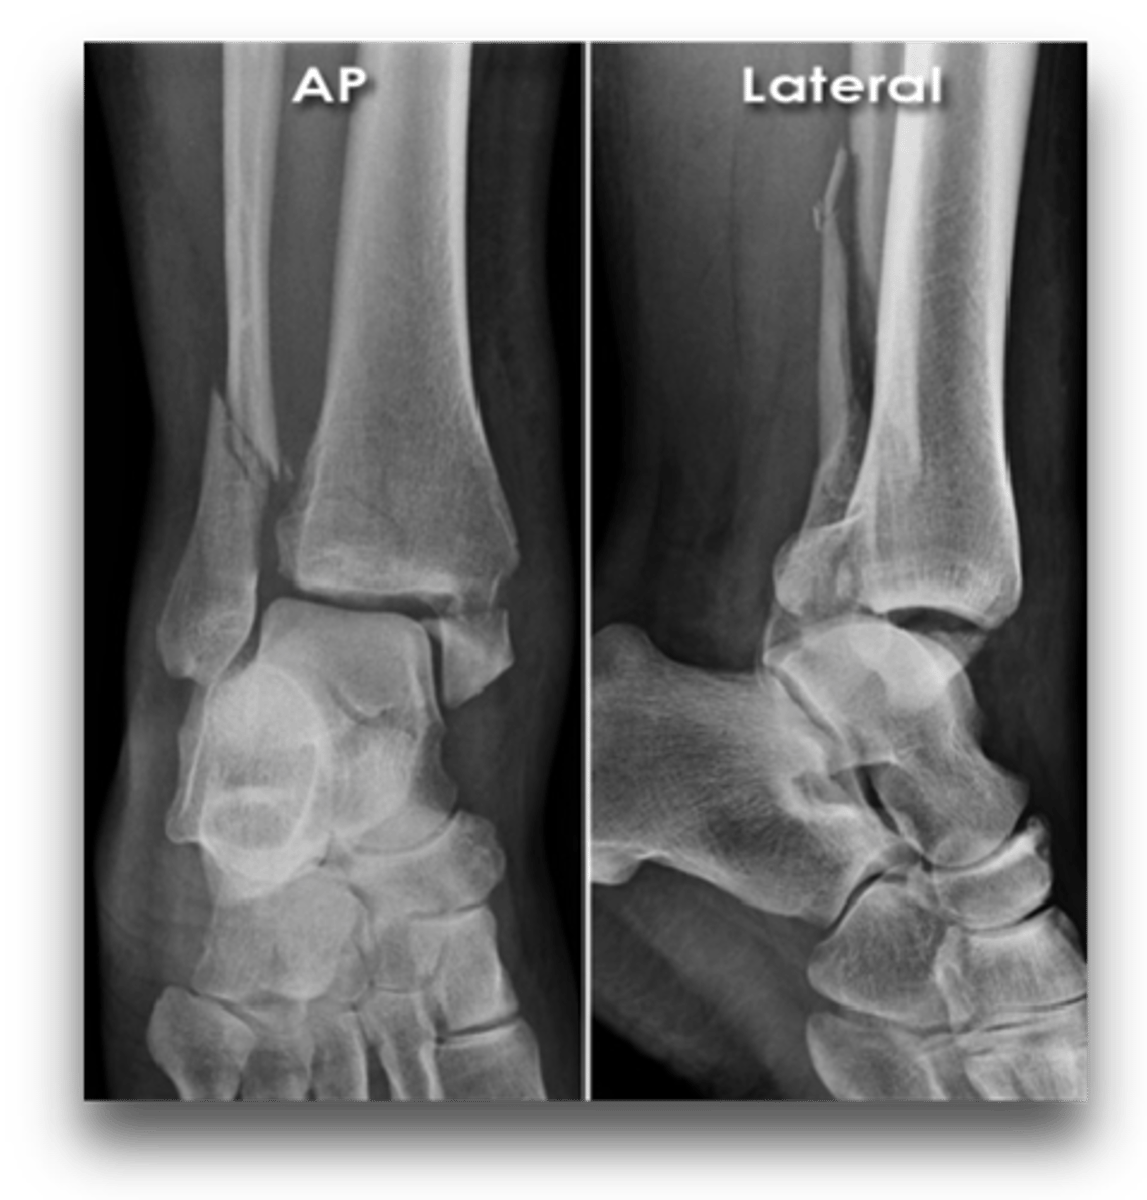

Fracture of the lateral malleolus, medial malleolus, and distal posterior tip of tibia

Trimalleolar fx

Complete fracture of distal fibula, frequently with fracture of medial malleolus

Pott's fx